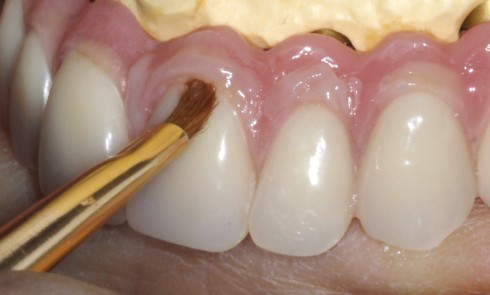

Article réservé à nos abonnés Prothèse complète implanto-portée: caractérisation de la fausse gencive en résine composite

Le succès d’une restauration prothétique, qu’elle soit fixe ou amovible, unitaire ou multiple, repose sur des exigences fonctionnelles mais aussi,...